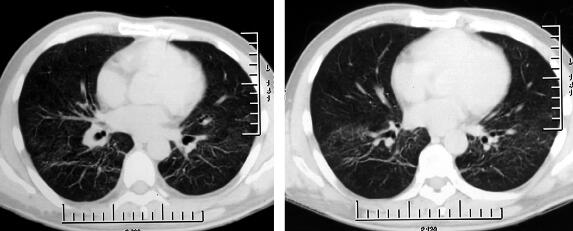

7.胸部影像学:

胸部CT示双肺点状高密度影,磨玻璃样改变(图1)。

图1

重要的检查结果有两项:①静脉血淋巴细胞百分比增高,CRP、ESR增高;②胸部影像学示双肺多发浸润影;结合患者的病史和体格检查结果,进一步支持感染性疾病——社区获得性肺炎(community acquired pneumonia,CAP)的诊断,但目前病原学尚不明确。